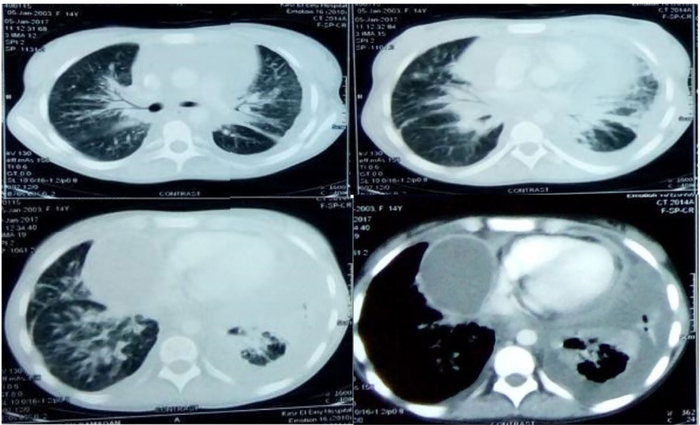

CT显示明显的心包积液,心包轻度增厚,左侧胸膜基底增厚,无心包填塞。此外还有双侧肺间质增厚(实变)斑片状区域和磨玻璃样覆盖[1]。立即行治疗性心包穿刺术显示纤维蛋白性渗出液,伴白细胞增多、主要是多形核淋巴细胞和丰富的淋巴浆细胞,其细菌培养和药敏实验均为阴性。

患者因呼吸短促、咯血、发烧和体重减轻再次入院。出现端坐呼吸、呼吸急促、发热(体温;38.5-39°C)和心动过速,无奇脉。颈部静脉充血且无搏动。心脏检查显示心脏裸露区域浊度增加,心音遥远,无杂音或心包摩擦音。胸部听诊双侧可见散在的爆裂音和哮鸣音。无下肢水肿、肝肿大或淋巴结肿大。除正细胞性贫血外,包括诊断性心包穿刺术和胸部 CT(图 1)在内的检查与初次入院时相似,伴有心包积液,心包粘连等。